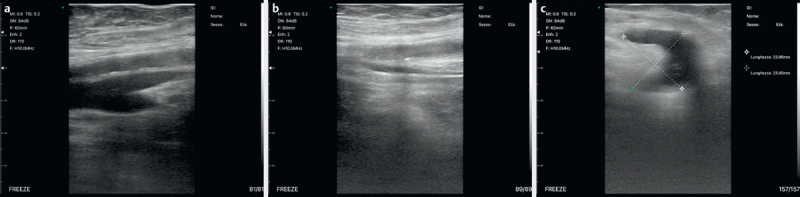

目的 手持式超声波(HH-US)可解答急诊中的简单临床问题。我们在就诊期间(MED)在病人床边(BED)用 HH-US 进行了传统超声检查(BED MED-US)。这项前瞻性研究的目的是评估 BED MED-US 的可靠性、其在帮助临床医生做出正确诊断方面的临床效果以及其节省时间和金钱的能力。材料和方法 在一个或多个地区对 1007 名患者(519 名男性;年龄:76.42 岁)进行了评估(从 2021 年 3 月到 2022 年 11 月)。通过临床和参考检查(胸部 RX/CT、腹部 CT、内窥镜检查等)确定最终诊断。对敏感性、特异性、LR+ 和 LR- 以及相应的 AUROC 进行了评估。HH-US 诊断分为:确诊(HH-US 发现的超声波征象证实了临床诊断)(CO)、排除(HH-US 在临床鉴别诊断中排除了其他病变的超声波征象)(EX)、病因诊断(HH-US 在临床可疑病例中得出诊断)(ET)或临床相关附带诊断(HH-US 诊断完全改变了患者的病程)(INC)。结果 HH-US 可靠性:true-pos:真阳性:752 例;真阴性:242 例;假阳性:7 例;假阴性:6 例:7; false-neg: 6 (sens: 99.1%, spec: 97.6%, LR+: 98.5; LR-: 00.15, AUROC: 0.997);临床影响:临床影响:CO-诊断:21%;EX:25%;ET:47%;INC:7%;节省的时间和金钱:约 35,572 分钟的工作时间和 9324 欧元。结论 BED MED-US 是一种可靠的临床成像系统,在诊断(47% 为病因诊断,7% 为偶然诊断)和人力资源管理方面都具有重要的临床影响。

Purpose Handheld ultrasound (HH-US) answers simple clinical questions in emergencies. We performed conventional US with HH-US at the patient's bedside (BED) during a medical visit (MED) (BED MED-US). The purpose of this prospective study is to estimate BED MED-US reliability, its clinical impact in helping the clinician to formulate correct diagnoses, and its ability to save time and money. Materials and Methods 1007 patients (519 M; age:76.42) were assessed (from March 2021 to November 2022) in one or more districts. Final diagnosis was determined with clinical and reference tests (chest RX/CT, abdominal CT, endoscopy, etc.). Sensitivity, specificity, LR+ and LR-, and corresponding AUROC were evaluated. HH-US diagnoses were classified as: confirmation (HH-US revealed the sonographic signs that confirmed the clinical diagnosis) (CO), exclusion (HH-US excluded the presence of the ultrasound signs of other pathologies, in the clinical differential diagnosis) (EX), etiological (HH-US reaches diagnosis in clinically doubtful cases) (ET), or clinically relevant incidental (HH-US diagnoses that change the patient's process completely) (INC). Results HH-US reliability: true-pos: 752; true-neg: 242; false-pos: 7; false-neg: 6 (sens: 99.1%, spec: 97.6%, LR+: 98.5; LR-: 00.15, AUROC: 0.997); clinical impact: CO-diagnosis: 21%; EX: 25%; ET: 47%; INC: 7%; saved time and money: approximately 35,572 minutes of work and 9324 euros. Conclusion BED MED-US is a reliable clinical imaging system, with an important clinical impact both in diagnosis (etiological in 47%, incidental in 7%) and in the management of personnel resources.